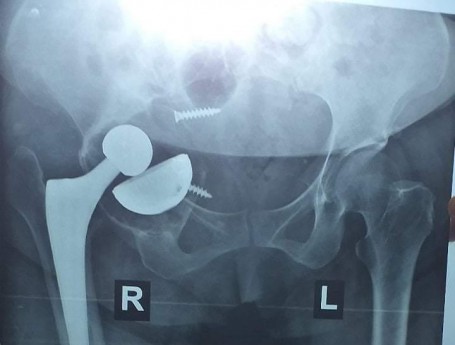

Revision Total Hip Arthroplasty